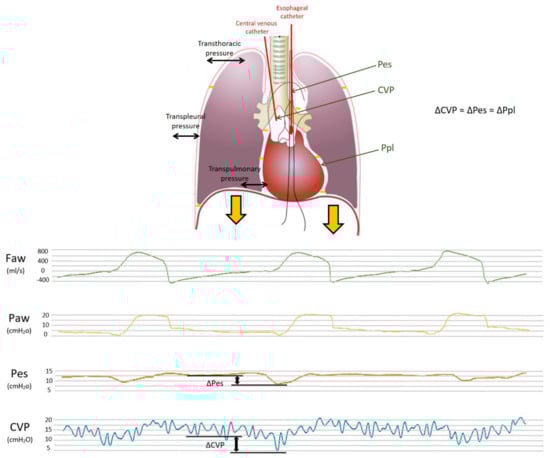

In particular, positive pressure mechanical inspiration increases intrathoracic pressure, thus causing a positive ΔCVP that reduces venous return. Conversely, spontaneous inspiration decreases intrathoracic pressure, thus causing a negative ΔCVP that increases venous return [30]. Indeed, this increase in venous return is limited; when the pressure drops below atmospheric pressure, the great veins collapse and develop a flow limitation. Therefore, based on these physiological assumptions, CVP appears to have respiratory oscillations that reflect intrathoracic (i.e., pleural) pressure changes. The extent of the respiratory swing in CVP was shown to be of a similar extent to that of Pes, which is also justified by the close anatomical position of the two measurement systems (as depicted in Figure 1 and Figure 2, upper panel).

In summary, CVP may represent a valid estimate of Ppl, similar to Pes, with the undeniable advantage of an almost ubiquitous presence of a central venous catheter in the critical care setting. This can provide an easy and rapid tool to evaluate partitioned respiratory mechanics and patient contribution during assisted breathing and guide titration of ventilatory support. The lower panel of Figure 2 shows the simultaneous recordings of flow, airway, esophageal and central venous pressures in a critically ill patient undergoing assisted mechanical ventilation. The use of ΔCVP as a surrogate of ΔPpl has been examined for decades, although it never became popular in the care of critically ill patients. In the following paragraphs, we summarize the findings of previous and recent papers that addressed this topic; the studies are divided into those reporting positive findings (i.e., CVP was found to be a reliable estimate of Pes or Ppl) and those reporting negative findings. Table 1 summarizes the factors influencing the relationship between CVP and pleural pressure; Table 2 reports the setting, methods and main findings of the studies included in the present review, and Table 3 summarizes the main biases and the limits of agreement of the different studies.

Figure 2. Upper panel: Model of the respiratory system and transmission of pleural pressure during inspiration. The respiratory system is composed of the lungs and the chest wall in series. The figure shows the different pressures within the system and the relative distending forces (in black). The difference between the alveolar and atmospheric pressure, i.e., the transthoracic pressure, is the pressure that distends both the lungs and the chest wall; the transpleural pressure (i.e., pleural minus atmospheric) is the pressure needed to distend the chest wall, whereas the transpulmonary pressure (i.e., airway minus pleural) is the pressure that distends the lungs. The thick, orange arrows depict the downward displacement of the diaphragm during inspiration, which lowers the pleural pressure (orange minus signs). This negative pleural pressure swing (ΔPpl) diffuses into the intrathoracic space and is transmitted through the esophagus to the balloon-tipped esophageal catheter (ΔPes) and through the superior vena cava to the central venous catheter (ΔCVP). Pes, esophageal pressure; Ppl, pleural pressure; CVP, central venous pressure. Lower panel: Pressure waveforms for CVP, Pes and Paw. Central venous pressure swings (CVP, blue wave), esophageal pressure swings (Pes, orange wave), airway pressure swings (Paw, yellow wave) and flow (Faw, green wave) during assisted mechanical ventilation.